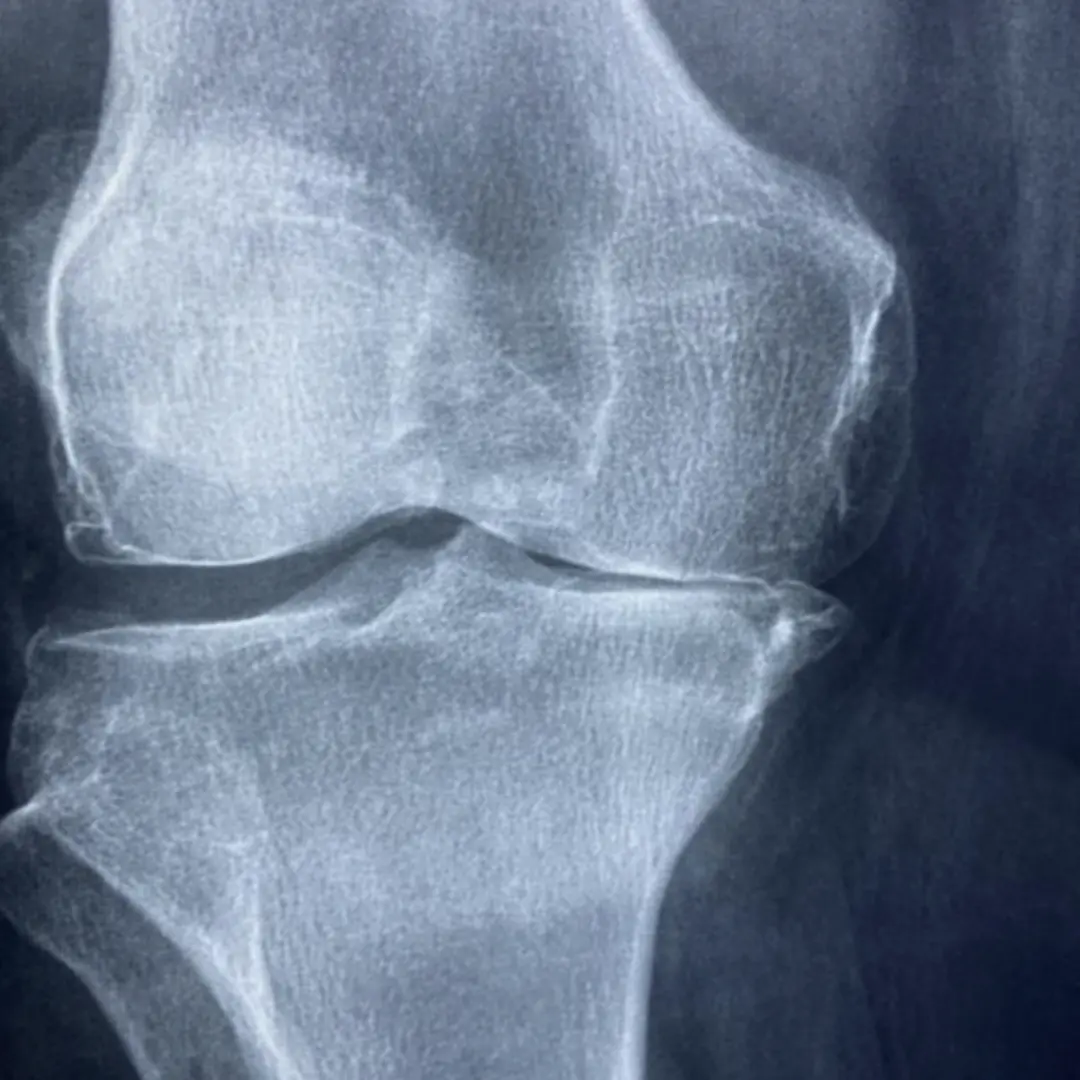

- 골관절염 환자:

- 관절 통증 완화 및 기능 개선에 도움을 받을 수 있어요.

- 관절 건강이 염려되는 노년층:

- 연골 손실을 예방하고 관절 건강을 유지하는 데 도움을 받을 수 있어요.

- 관절을 많이 사용하는 운동선수:

- 관절 손상을 예방하고 운동 능력을 향상시키는 데 도움을 받을 수 있어요.

- 평소 관절에 불편함을 느끼시는분:

- 관절의 불편함과 통증을 완화 하는데 도움을 받을 수 있습니다.